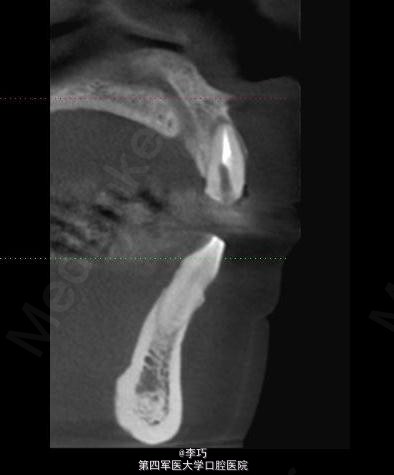

行曲面断层片和CBCT模拟植入